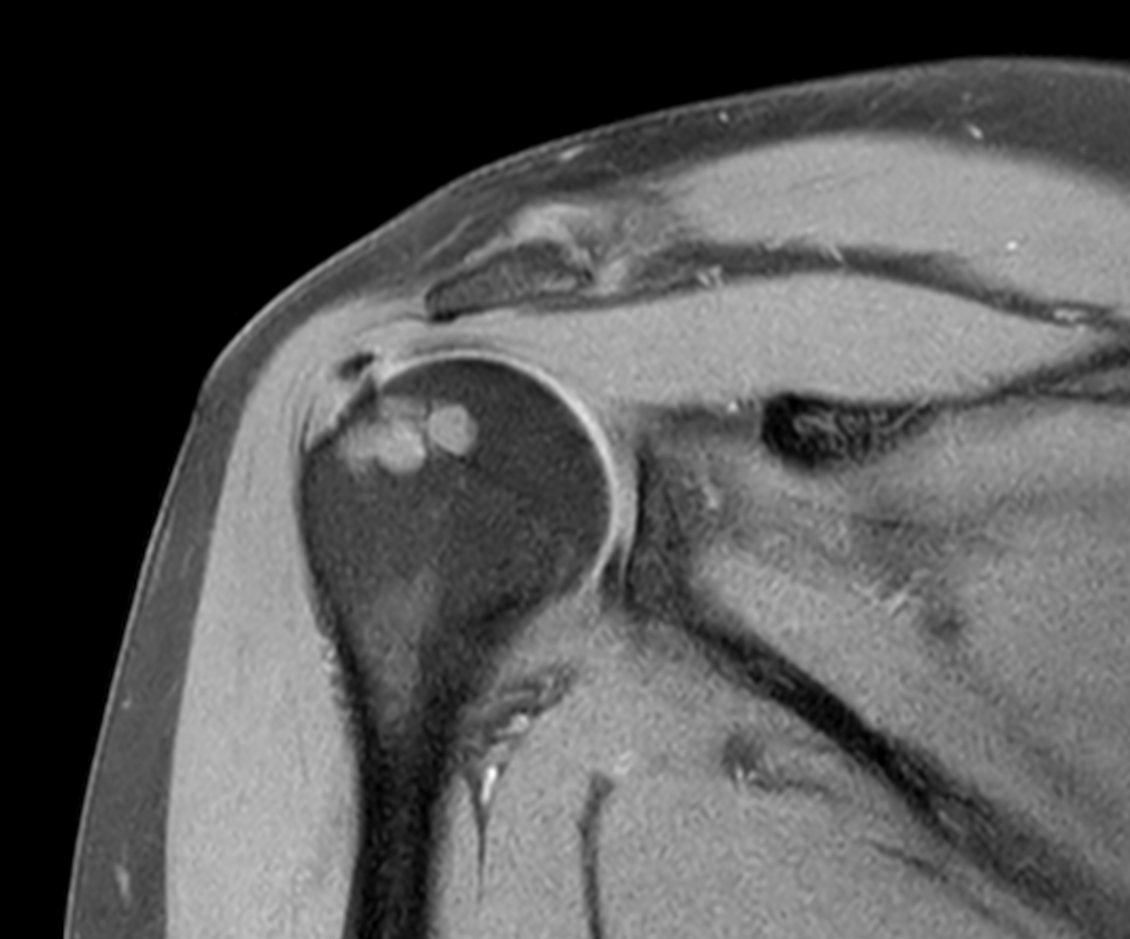

Axial PDw TSE

Axial T1w TSE